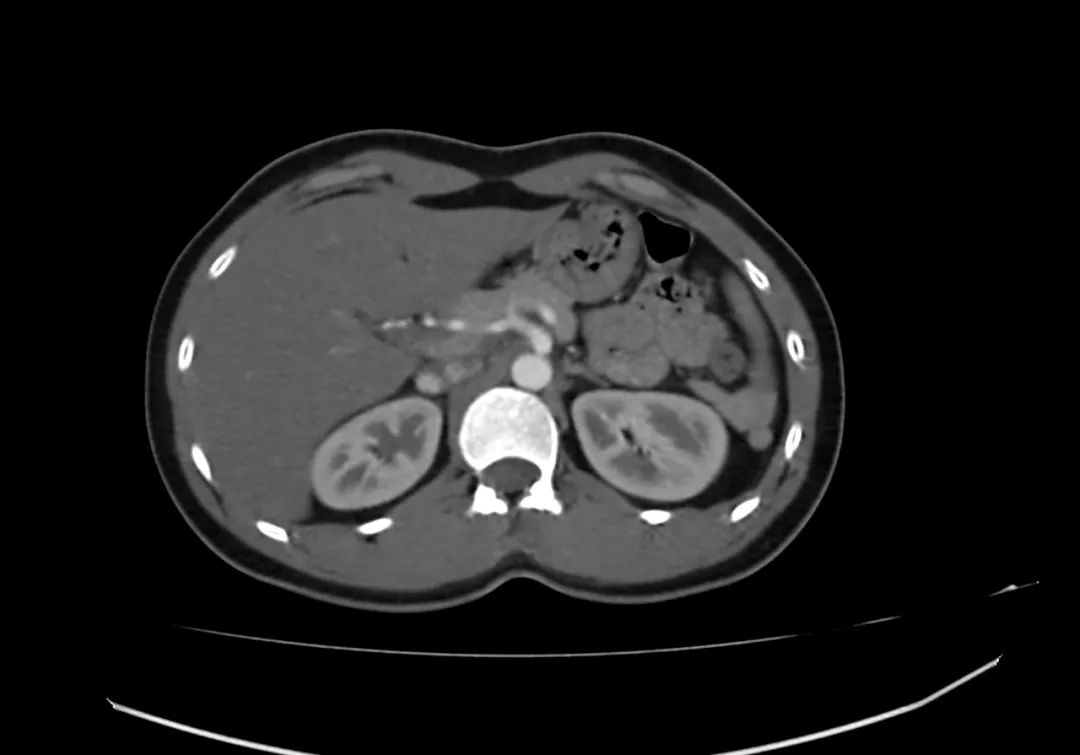

动脉期上腹部轴向增强图像显示胰腺完全包围十二指肠第二部,与完全性环状胰腺一致。

环状胰腺是由腹芽不旋转导致十二指肠被胰腺不同程度包裹的结果。完全性环状胰腺出现在新生儿有梗阻,并可偶然发现在成人,胰腺炎可能是成人的一种表现特征。